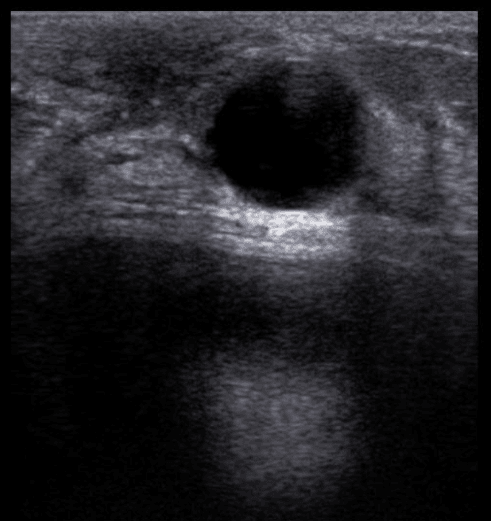

cisto no ultrassom de mamas

Ultrassonografia de mamas demonstrando um cisto simples. Imagem tipicamente benigna.